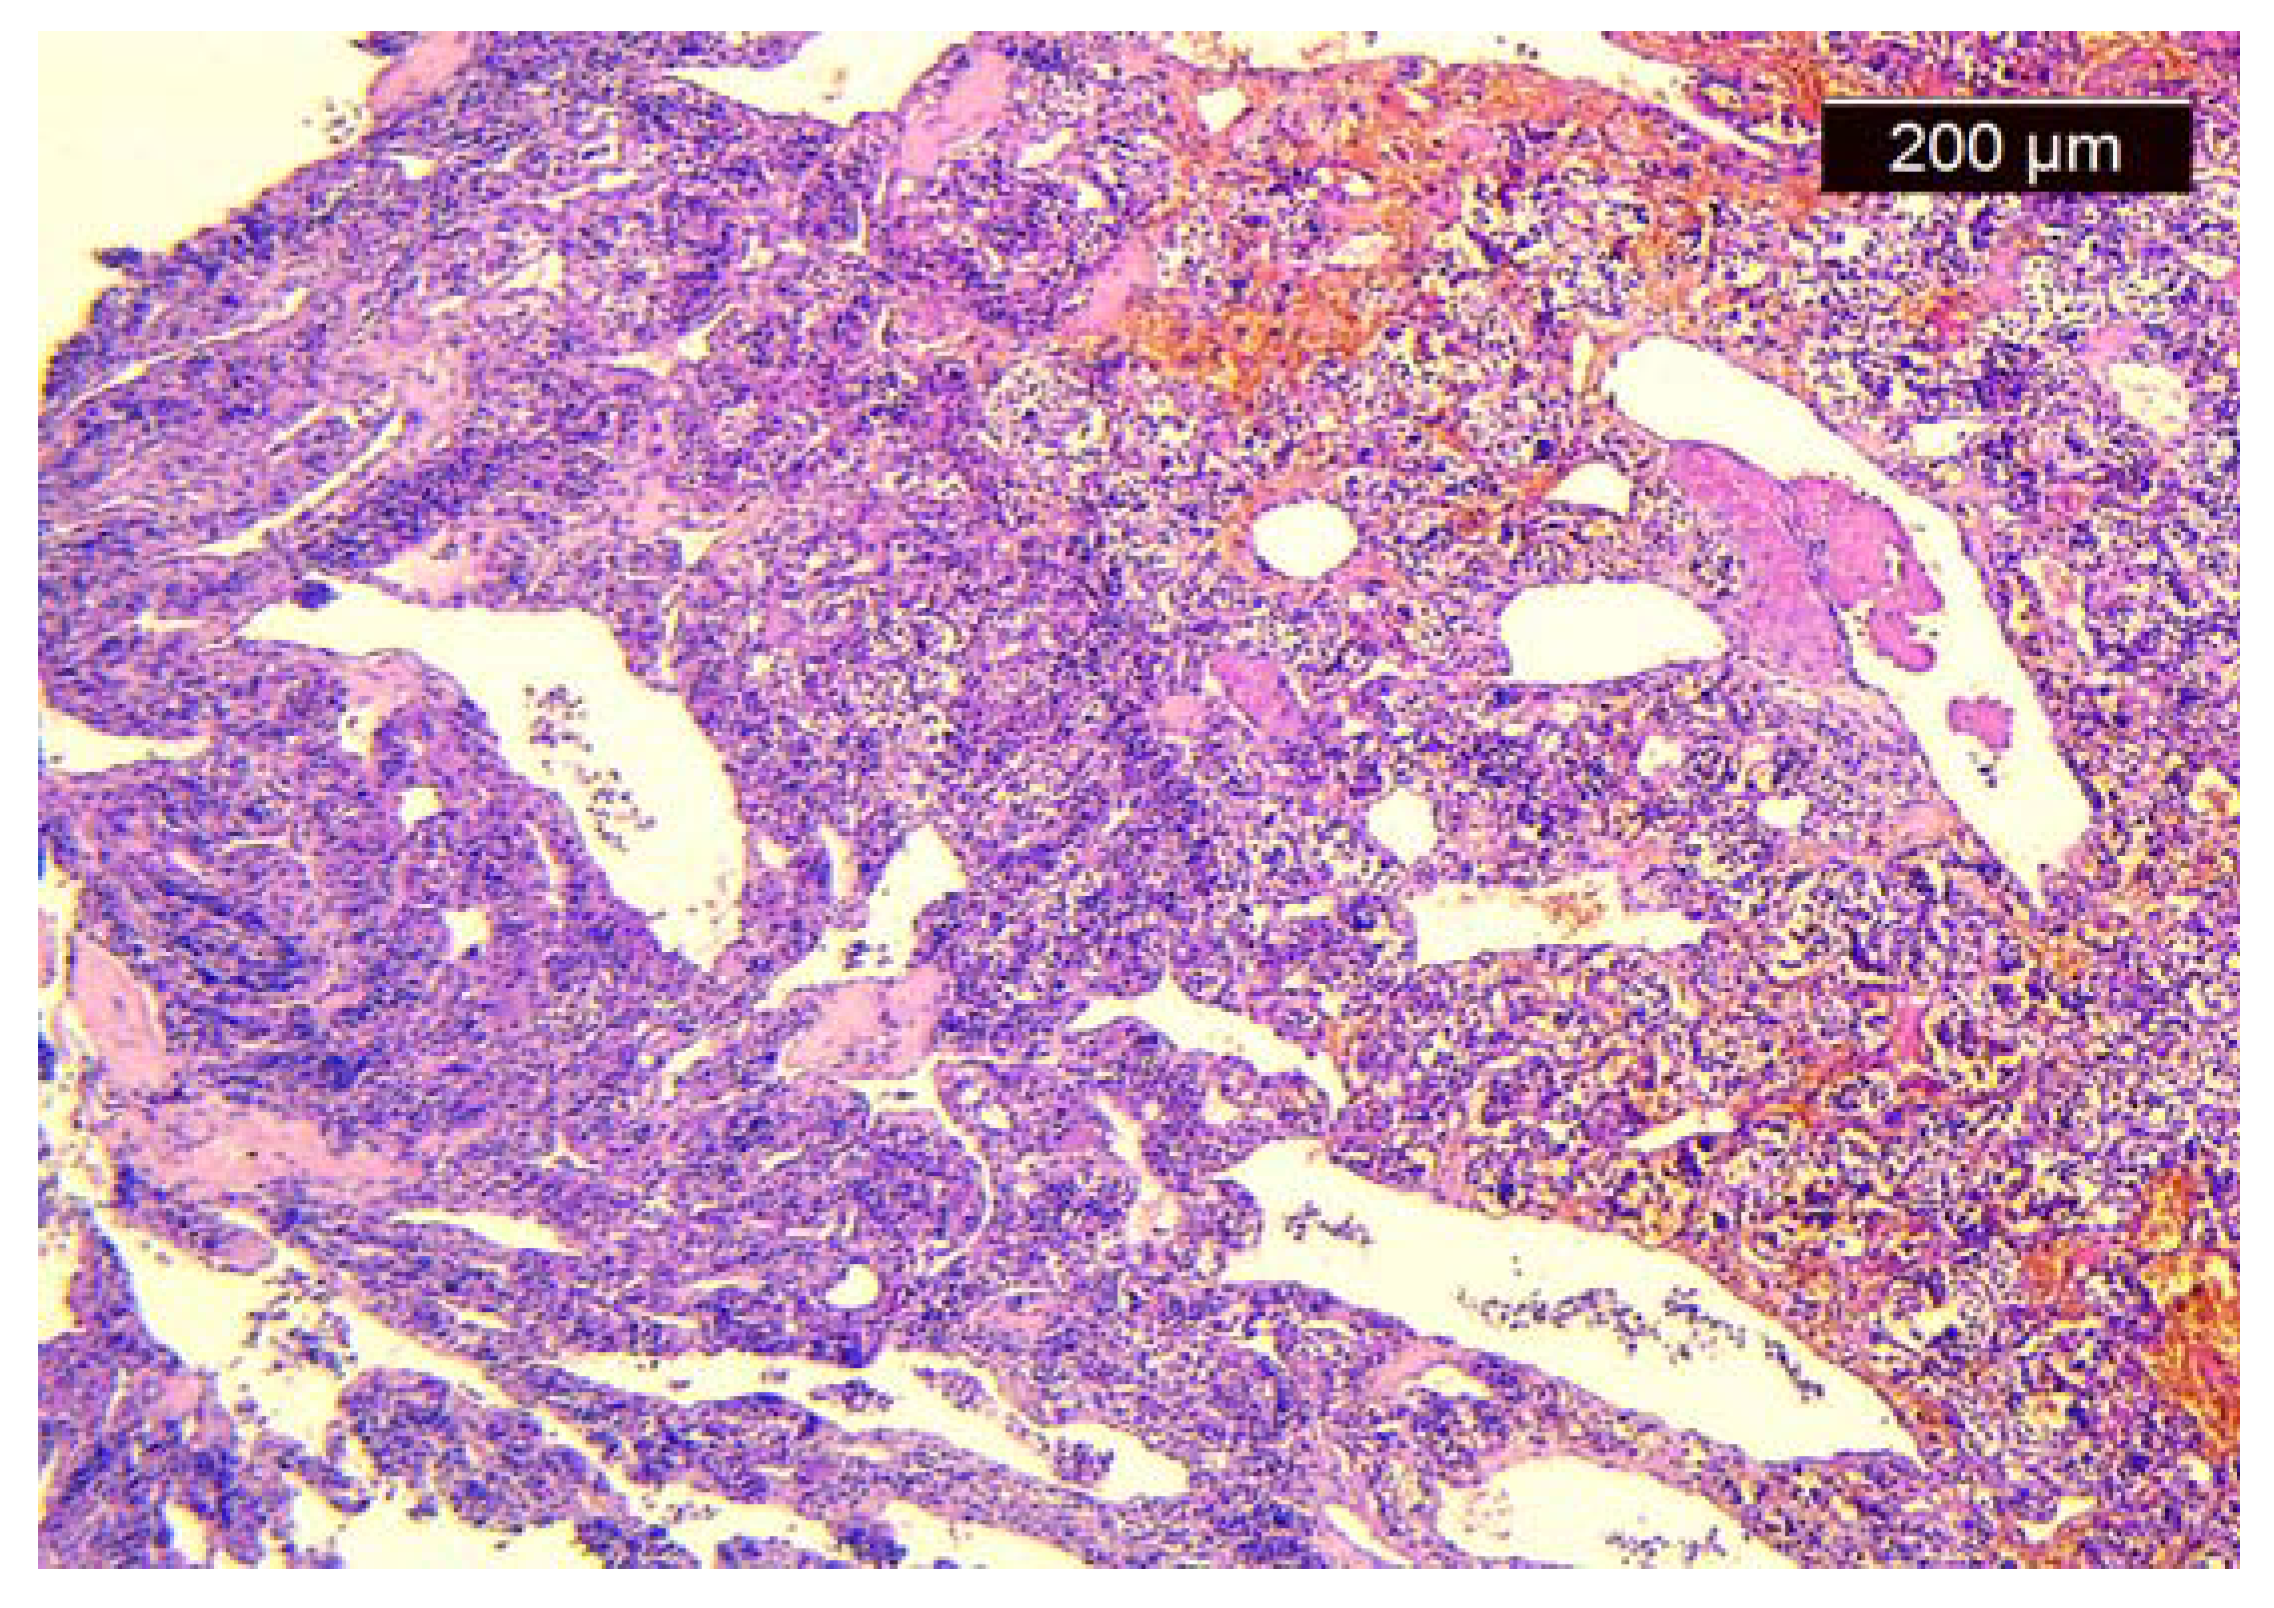

We took multiple pieces from the tumor with the help of a flexible endoscope with a working channel, preserved them in formalin recipient, and handed them to the anatomopatology department. The biopsy revealed the absence of dysplasia, the presence of the “Zellballen” pattern, cubic cells gathered in nest-like groups, rich vascularization, and a Ki67 of 50%, all suggesting a laryngeal paraganglioma (Figure 3).

Figure 3.

Histological aspect of the tumor.